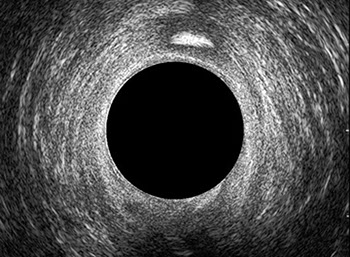

L’ecografia transanale è un esame diagnostico per immagini che consiste nell’introduzione di un trasduttore ad ultrasuoni. Le immagini qualitativamente migliori del canale anale sono ottenute usando un trasduttore rotante, montato in un manipolo rigido, che fornisce un’immagine a 360°. Con le apparecchiature più moderne è anche possibile ottenere immagini tridimensionali.

L’ecografia transanale permette di distinguere la sottomucosa che riveste il canale anale, lo sfintere anale interno, e lo sfintere anale esterno.